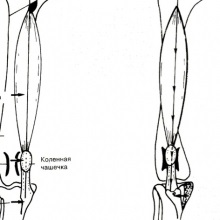

Valgus deformitás (kéztő valgus) - az ilyen típusú törzs a frontális síkban, szögben amely nyitott kifelé (oldalirányban). Relevanciája a témát. Az összes ortopédiai problémák mellső végtag gus deformitás az alkar csontjai bekövetkezett 18% -ában.

Kezelése zavar a patella konzervatív és operatív. Konzervatív (nem műtéti) kezelés javallt általában szakaszos habituális ficam hiányában más látható vagy mérhető X-ray.

Etiológia. Okokból előfordulása diszlokációk a térd csésze osztható veleszületett, örökletes és traumás tüneteket. Veleszületett.